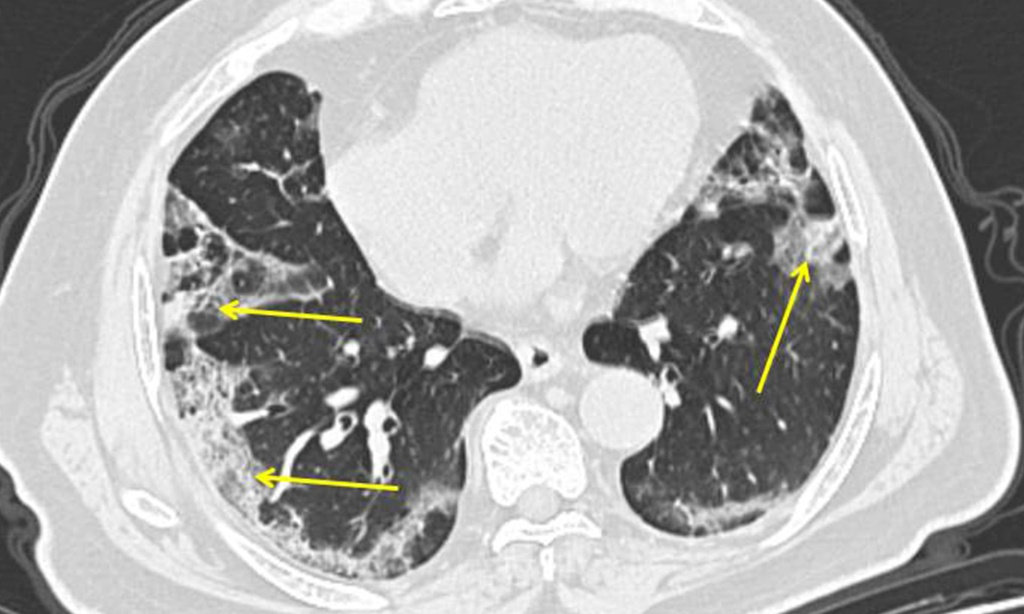

Viêm phổi do Covid-19 ảnh hưởng toàn bộ phổi

Giáo sư Jenkins cho biết viêm phổi do SARS-CoV-2 gây ra khác biệt với các trường hợp viêm phổi khác thường buộc người bệnh phải nhập viện.

Ông Wilson nói có bằng chứng cho thấy viêm phổi do Covid-19 có thể đặc biệt nghiêm trọng. Viêm phổi ở các ca nhiễm Covid-19 thường ảnh hưởng tới toàn bộ phổi, thay vì chỉ những phần nhỏ của phổi.